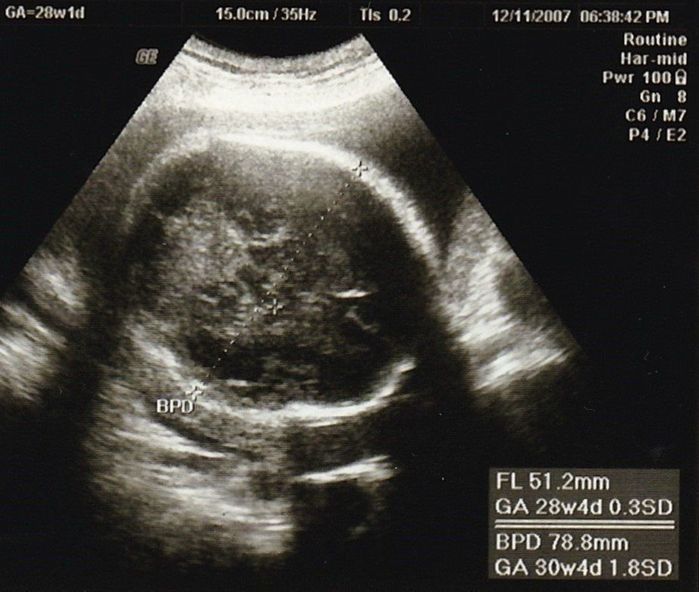

妊娠28週目のエコー写真

この辺から、少し動くだけで息切れするようになり、寝ても起きても息苦しさを感じていました。思ったより体力がなくなり、マタニティーヨガに通ったり、胎教にとクラシックや童謡や英語の曲などを聴いたりして気分転換を心がけて過ごしました。

妊娠30週目のエコー写真

赤ちゃんの大きさは標準の真ん中あたり。胎盤の位置や羊水の量も正常、母子ともに問題はありませんでした。